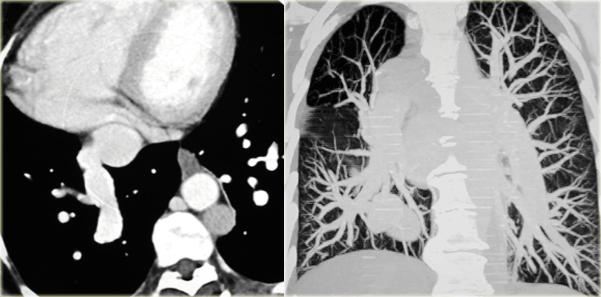

Left Superior Vena Cava

Describe the images on the left and then continue reading.

On the left side there is a vascular structure, that runs inferiorly below the level of the left hilum and enters into a dilated coronary sinus.

The diagnosis is left or double superior vena cava.

Left Superior Intercostal Vein.

This is an anastomosis between the accessory hemiazygos vein and the left brachiocephalic vein.

It courses along the lateral margin of the aortic arch (‘aortic nipple’).

It is a normal variant and if you look for this structure you will frequently notice it.

On the left a patient with a left superior intercostal vein.

Notice the ‘aortic nipple sign’.

On the left another example of a left superior intercostal vein.

It courses along the lateral margin of the aortic arch from the the accessory hemiazygos vein to the left brachiocephalic vein.